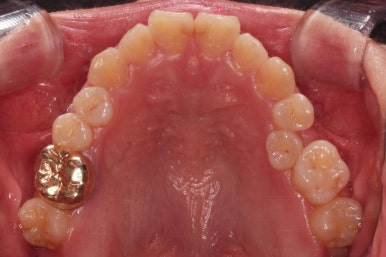

이번 부산교정 환자분은 교정치료 첫 단꼐로 악궁확장장치를 했는데요.

일반 확장 장치로는 불가하다는 판단이 되어 미니스크류를 활용한 악궁확장장치(MARPE)를 해주었어요.

이번 환자분은 일반 악궁확장장치로는 불가하다는 판단에 미니스크류를 이용한 악궁확장을 시행했고요.

입천장에 장치를 3개월 가량 유지하는 동안 치아에 브라켓을 부착하여 가지런하게 해줍니다.

이번 환자분이 선택하신 장치는 눈에 많이 띄는 윗니는 자가결찰 세라믹(데이몬 클리어, Damon clear), 아랫니는 자가결찰 메탈(엠파워 메탈, Empower metal)을 사용했어요.